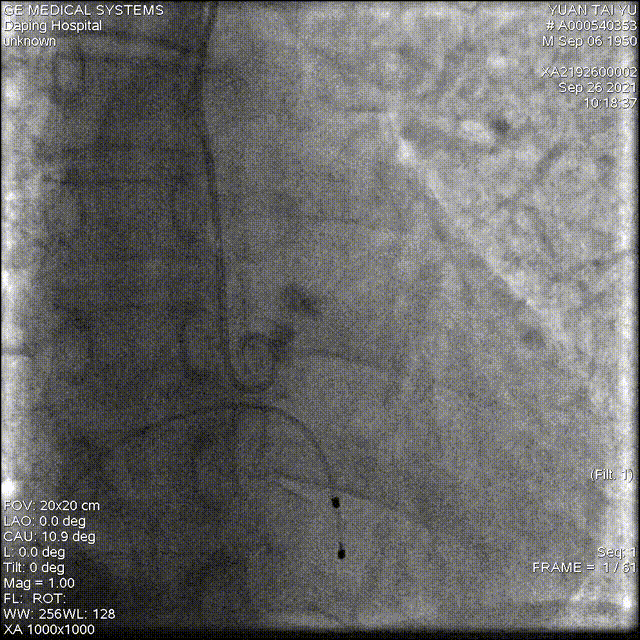

以 Seldinger法穿刺右桡动脉,使用Pig造影导管行主动脉根部造影

20mm球囊预扩,有腰无漏

造影确定释放位置

释放成功,但存在中度瓣周漏,经20mm球囊后扩,造影见微量瓣周漏,较前明显好转